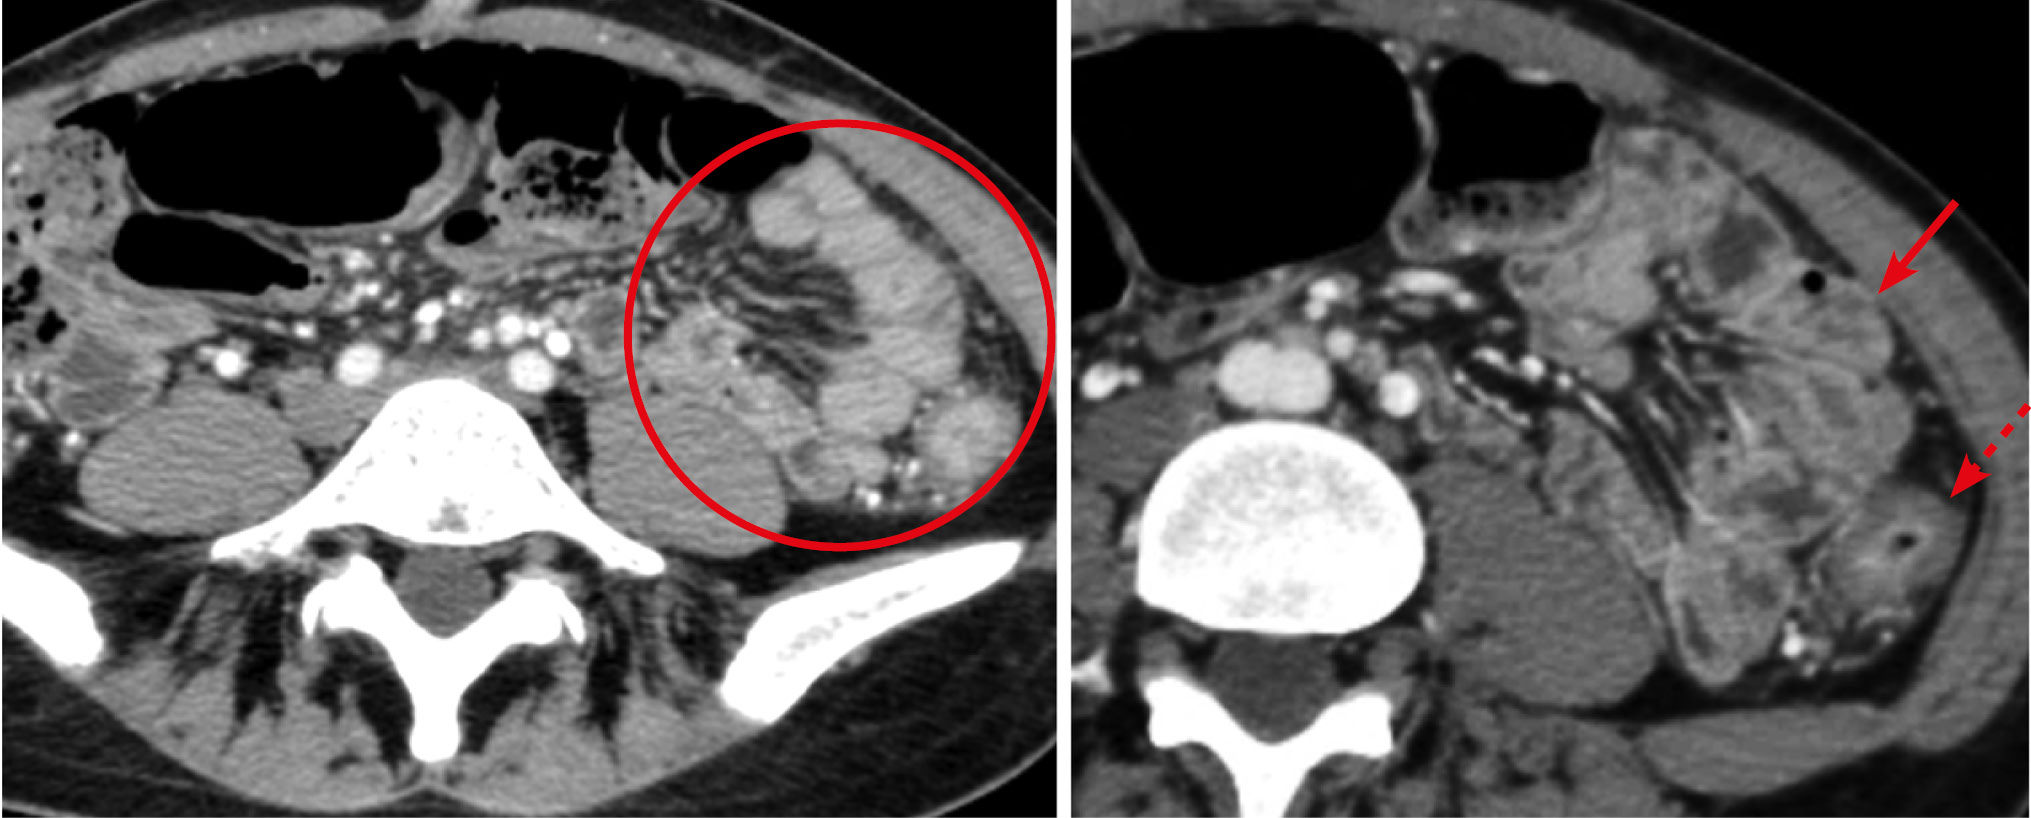

Рис. 9. Больная, 53 года. МСКТ: рак дистального отдела подвздошной кишки. Тонкокишечная непроходимость

Примечание. А — аксиальная томограмма, Б — сагиттальная реконструкция томограммы. Артериальная фаза контрастного усиления. В дистальном отделе подвздошной кишки на протяжении 10 см определяется экзофитное образование, суживающее просвет (стрелки). Опухоль трансмурально накапливает контрастный препарат. В тонком кишечнике имеются признаки компенсированной тонкокишечной непроходимости.

Рис. 10. Больной, 48 лет. МСКТ: саркома подвздошной кишки

Примечание. А — нативное исследование, Б — артериальная фаза контрастного усиления. По брыжеечному краю стенки подвздошной кишки наблюдается сегментарное утолщение стенки (стрелка), которое при контрастном усилении накапливает контрастный препарат равномерно и трансмурально. В прилежащей части брыжейки определяется разрастание элементов опухолевой ткани.